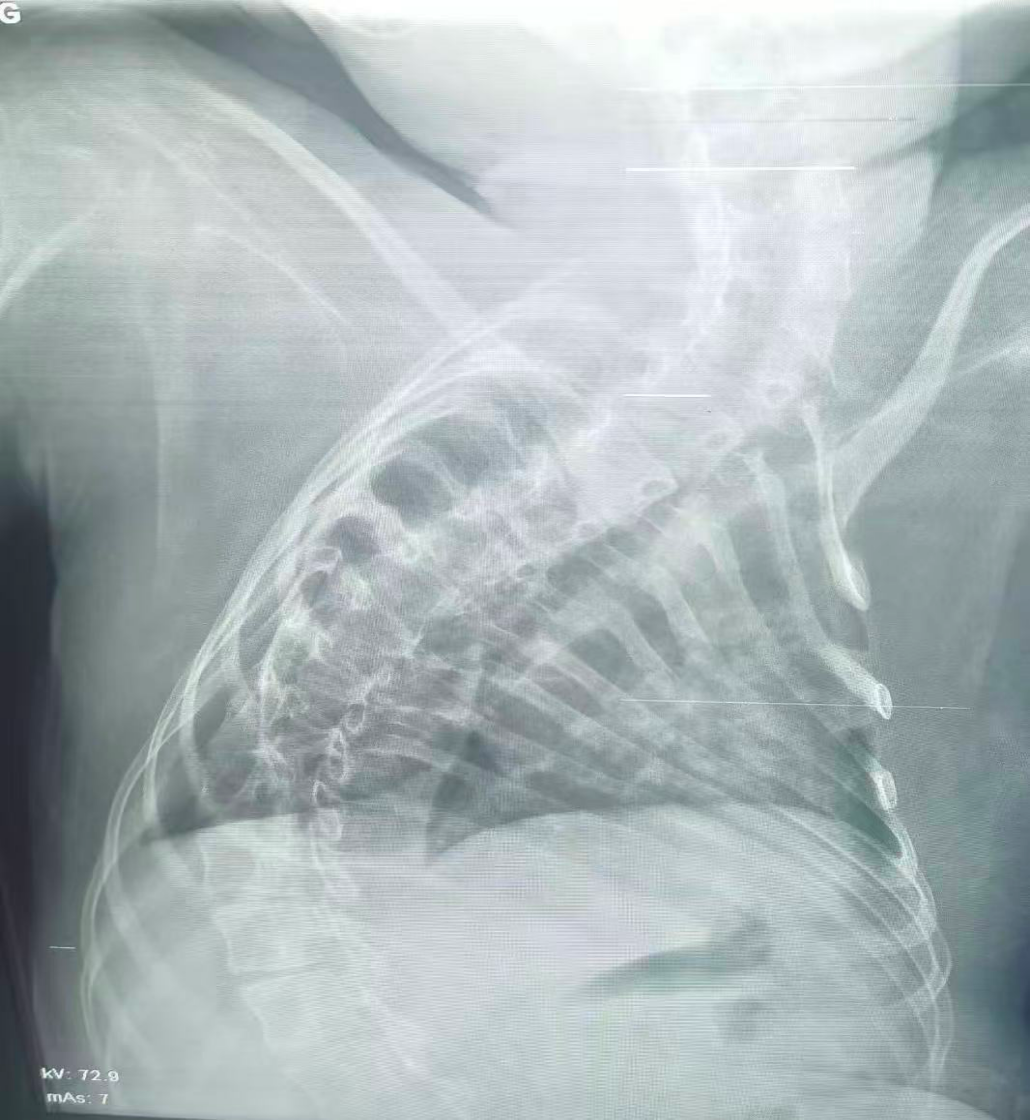

治療前

該患兒因患脊髓性肌萎縮癥長期臥床,呼吸肌已嚴重無力,自主呼吸微弱且?guī)缀鯁适Э人耘盘的芰?,此次并發(fā)支氣管肺炎后,肺部感染迅速加重,生命已然懸于一線。更棘手的是,嚴重的脊柱側彎使患兒胸廓畸形、氣道解剖結構明顯移位,常規(guī)纖支鏡進鏡路徑完全失效,扭曲狹窄的氣道如同縱橫交錯的“迷宮”,每一步操作都必須精準到毫米級別。

體位擺放則成為另一道“攔路虎”,既要滿足纖支鏡操作需求,又要避免側彎脊柱受壓、防止肌萎縮引發(fā)關節(jié)脫位,每個角度都得反復測算。同時,還需直面層層疊加的術中危機:因患兒呼吸肌功能幾乎喪失,纖支鏡占用狹窄氣道空間后,缺氧、二氧化碳潴留及急性呼吸衰竭、心跳驟停風險陡增;灌洗過程中若液體殘留將加重肺部感染,而患兒免疫力低下,導致敗血癥的風險顯著升高。